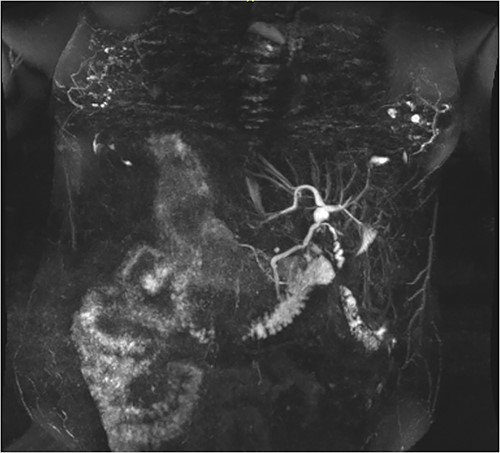

Following examination, a magnetic resonance cholangiopancreatography (MRCP) test was requested to exclude choledocholithiasis. 24 hours later, this confirmed gallstones, with 10 mm saccular dilatations near the hilar confluence (Figs 1 and 2). This dilatation was non-progressive according to previous scans, with unaffected pancreatic and intrahepatic ducts. Dilated portal vessels and varices were discovered to be directly communicating with the gallbladder fossa, suggestive of portal venous communication.

Coronal MRCP scan demonstrating a 10 mm area of saccular duct dilatation at the hilar confluence. Large, dilated vessels/varices surrounding the gallbladder fossa can also be appreciated.